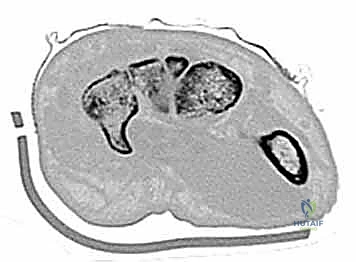

- الأشعة المقطعية (CT Scan): المعيار الذهبي لتشخيص كسور عظام الرسغ المخفية وتحديد حجم التفتت والتزحزح.

3. إرجاع العظم إلى وضعه التشريحي (Reduction)

تحت توجيه الأشعة السينية المباشرة داخل غرفة العمليات (C-arm)، يتم إرجاع قطع العظم المكسورة إلى مكانها الطبيعي بدقة متناهية لا تقبل الخطأ حتى بمليمتر واحد، لأن أي اعوجاج سيؤدي إلى خشونة مبكرة في المفصل.

عامل بناء (40 عاماً) تعرض لسقوط جسم ثقيل على يده، مما أدى إلى كسر مفتت في العظم الكبير (Capitate). بفضل التدخل الجراحي السريع باستخدام تقنية التثبيت بالمسامير المدفونة تحت توجيه الأشعة، تمكن الدكتور هطيف من إعادة بناء العظم بدقة تشريحية مذهلة، مما أنقذ المريض من خشونة مبكرة كانت ستمنعه من ممارسة مهنته للأبد.